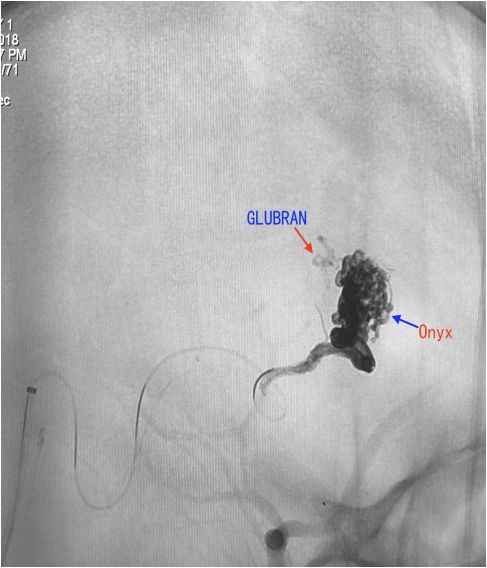

全麻插管,右侧股动脉置6F鞘,右侧颈内静脉置5F鞘。右侧颈内动脉放置6F导引导管,路图下,在Traxcess14微导丝导引下把Scepter 4*10球囊放置在畸形血管团供血动脉处,充盈球囊,造影,见畸形血管团不显影。然后通过颈静脉鞘,5F125cmsofia导引导管在marathon和Traxcess14导引下超选至直窦,marathon在Traxcess14导引下超选至畸形血管团静脉起始段内。充盈Scepter球囊,marathon静脉内造影,造影剂淤滞,予以充盈球囊后通过静脉内注胶,但发现胶依然快速向静脉移位,考虑仍有供血动脉球囊仍未完全覆盖,调整球囊并通过球囊导管造影发现该畸形血管团由相对独立两部分组成。重新调整球囊并完全覆盖供血动脉后再次通过静脉内注Onyx胶,较弥散良好。但因畸形血管团由两个相对独立部分组成,胶未能弥散另一部分畸形血管团内,予以通过球囊导管动脉入路栓塞,Scepter球囊导管超选供血动脉,予以16.6%GLUBRAN胶栓塞,造影见畸形血管团完全治愈性栓塞,术中控制性降压(比打胶前将低20mmHg),并中和肝素术后CT未见出血,术后患者清醒,功能无障碍。